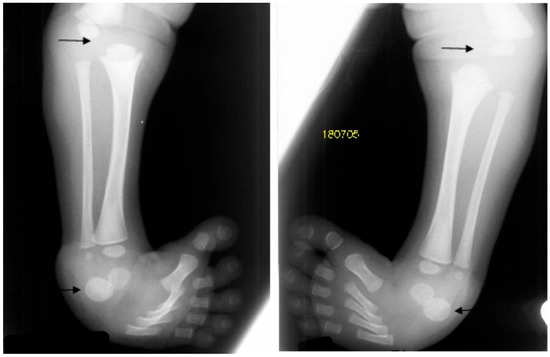

Figure 3.

AP knees radiograph of a 5-month-old boy with Larsen syndrome showing bilateral knee dislocations (arrows) associated with under tubulation of the tibae and fibulae. Note the fragmented/deformed epiphyses and that the right tibia is medially subluxated. Note bilateral talipes equinivarus associated with double ossifications of the calcaneus (arrows).